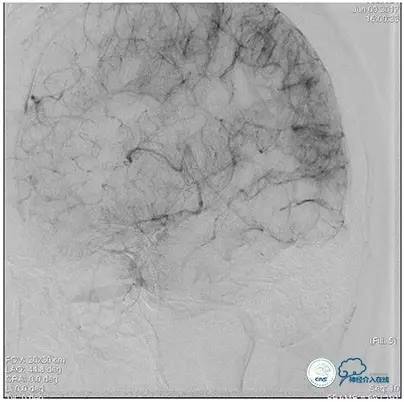

静脉淤滞